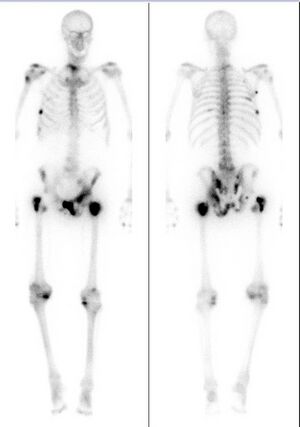

Bone scintigraphy scan of a man with metastatic prostate cancer. Dark spots indicate metastases along the pelvis, ribs, and shoulder.

قد ينتشر سرطان البروستاتي إلى الأعضاء المجاورة والعظام ومن الممكن أن يهدد الحياة.

الألم

على الرغم من أن المراحل المبكرة من سرطان البروستاتي غير مؤلمة، ولكنها حالما تصيب العظام فقد يظهر ألم شديد، والعلاجات الموجهة لتقليص السرطان قد تساعد على تخفيف الألم.

Extent of cancer spread is assessed by MRI or PSMA scan – a positron emission tomography (PET) imaging technique where a radioactive label that binds the prostate protein prostate-specific membrane antigen is used to detect metastases distant from the prostate.[12][8] CT scans may also be used, but are less able to detect spread outside the prostate than MRI. Bone scintigraphy is used to test for spread of cancer to bones.[12]